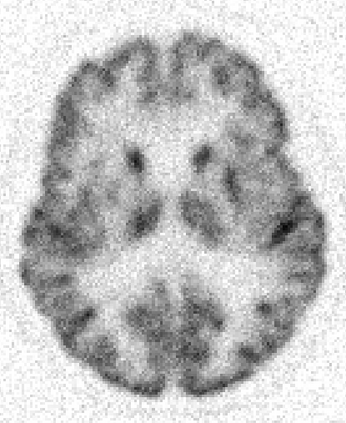

Due to various physical degradation factors and limited counts received, PET image quality needs further improvements. The denoising diffusion probabilistic models (DDPM) are distribution learning-based models, which try to transform a normal distribution into a specific data distribution based on iterative refinements. In this work, we proposed and evaluated different DDPM-based methods for PET image denoising. Under the DDPM framework, one way to perform PET image denoising is to provide the PET image and/or the prior image as the network input. Another way is to supply the prior image as the input with the PET image included in the refinement steps, which can fit for scenarios of different noise levels. 120 18F-FDG datasets and 140 18F-MK-6240 datasets were utilized to evaluate the proposed DDPM-based methods. Quantification show that the DDPM-based frameworks with PET information included can generate better results than the nonlocal mean and Unet-based denoising methods. Adding additional MR prior in the model can help achieve better performance and further reduce the uncertainty during image denoising. Solely relying on MR prior while ignoring the PET information can result in large bias. Regional and surface quantification shows that employing MR prior as the network input while embedding PET image as a data-consistency constraint during inference can achieve the best performance. In summary, DDPM-based PET image denoising is a flexible framework, which can efficiently utilize prior information and achieve better performance than the nonlocal mean and Unet-based denoising methods.